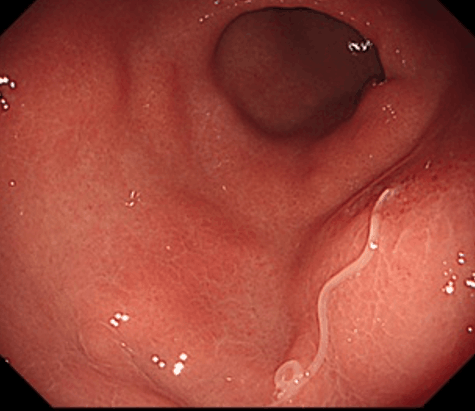

問診で胃アニサキス症が疑われる場合、胃カメラ(胃内視鏡検査)が第一選択となります。内視鏡により胃粘膜に刺入した長さ2~3cmの細長く白い虫体が確認され、それを鉗子で抜去することによって診断・治療を同時に行うことが可能です。

1.症状のある胃アニサキス症です。刺入部を中心に浮腫による隆起がみられます。